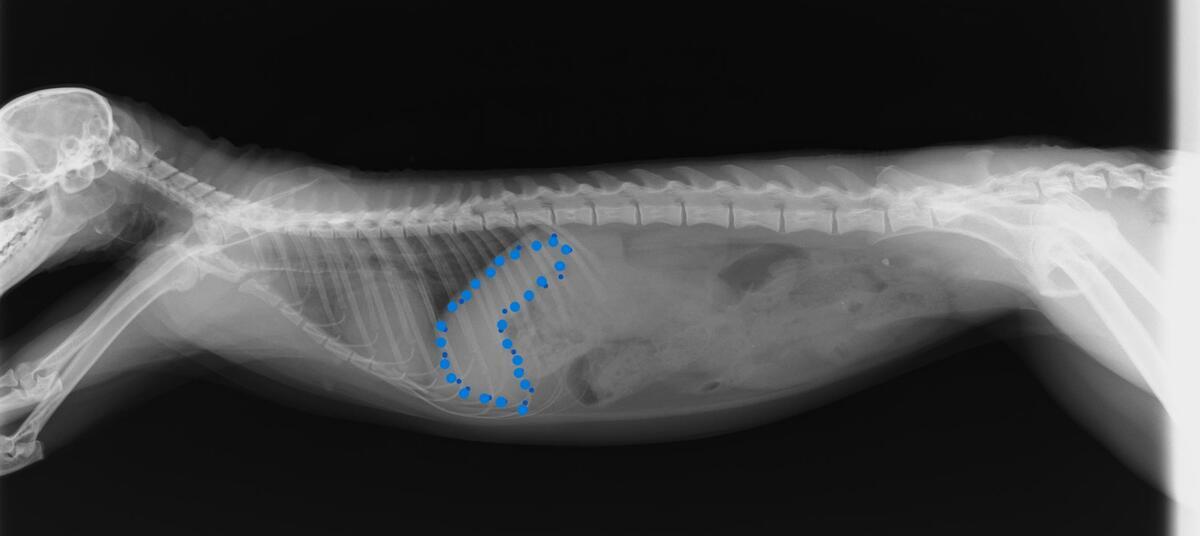

↓2022年のレントゲン写真(青い点が肝臓)。

↓2026年のレントゲン写真。